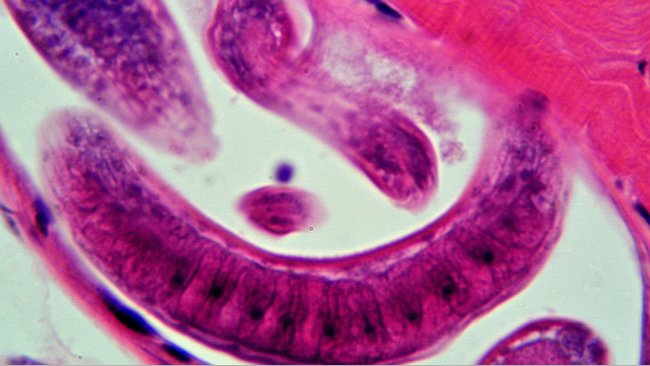

O Senasa e a Província reforçarão o trabalho conjunto para reduzir os casos de triquinose.

Casos de pessoas infectadas pela triquinose levou o SENASA na Argentina ao abate controlado de suínos em três granjas da província de Córdoba.